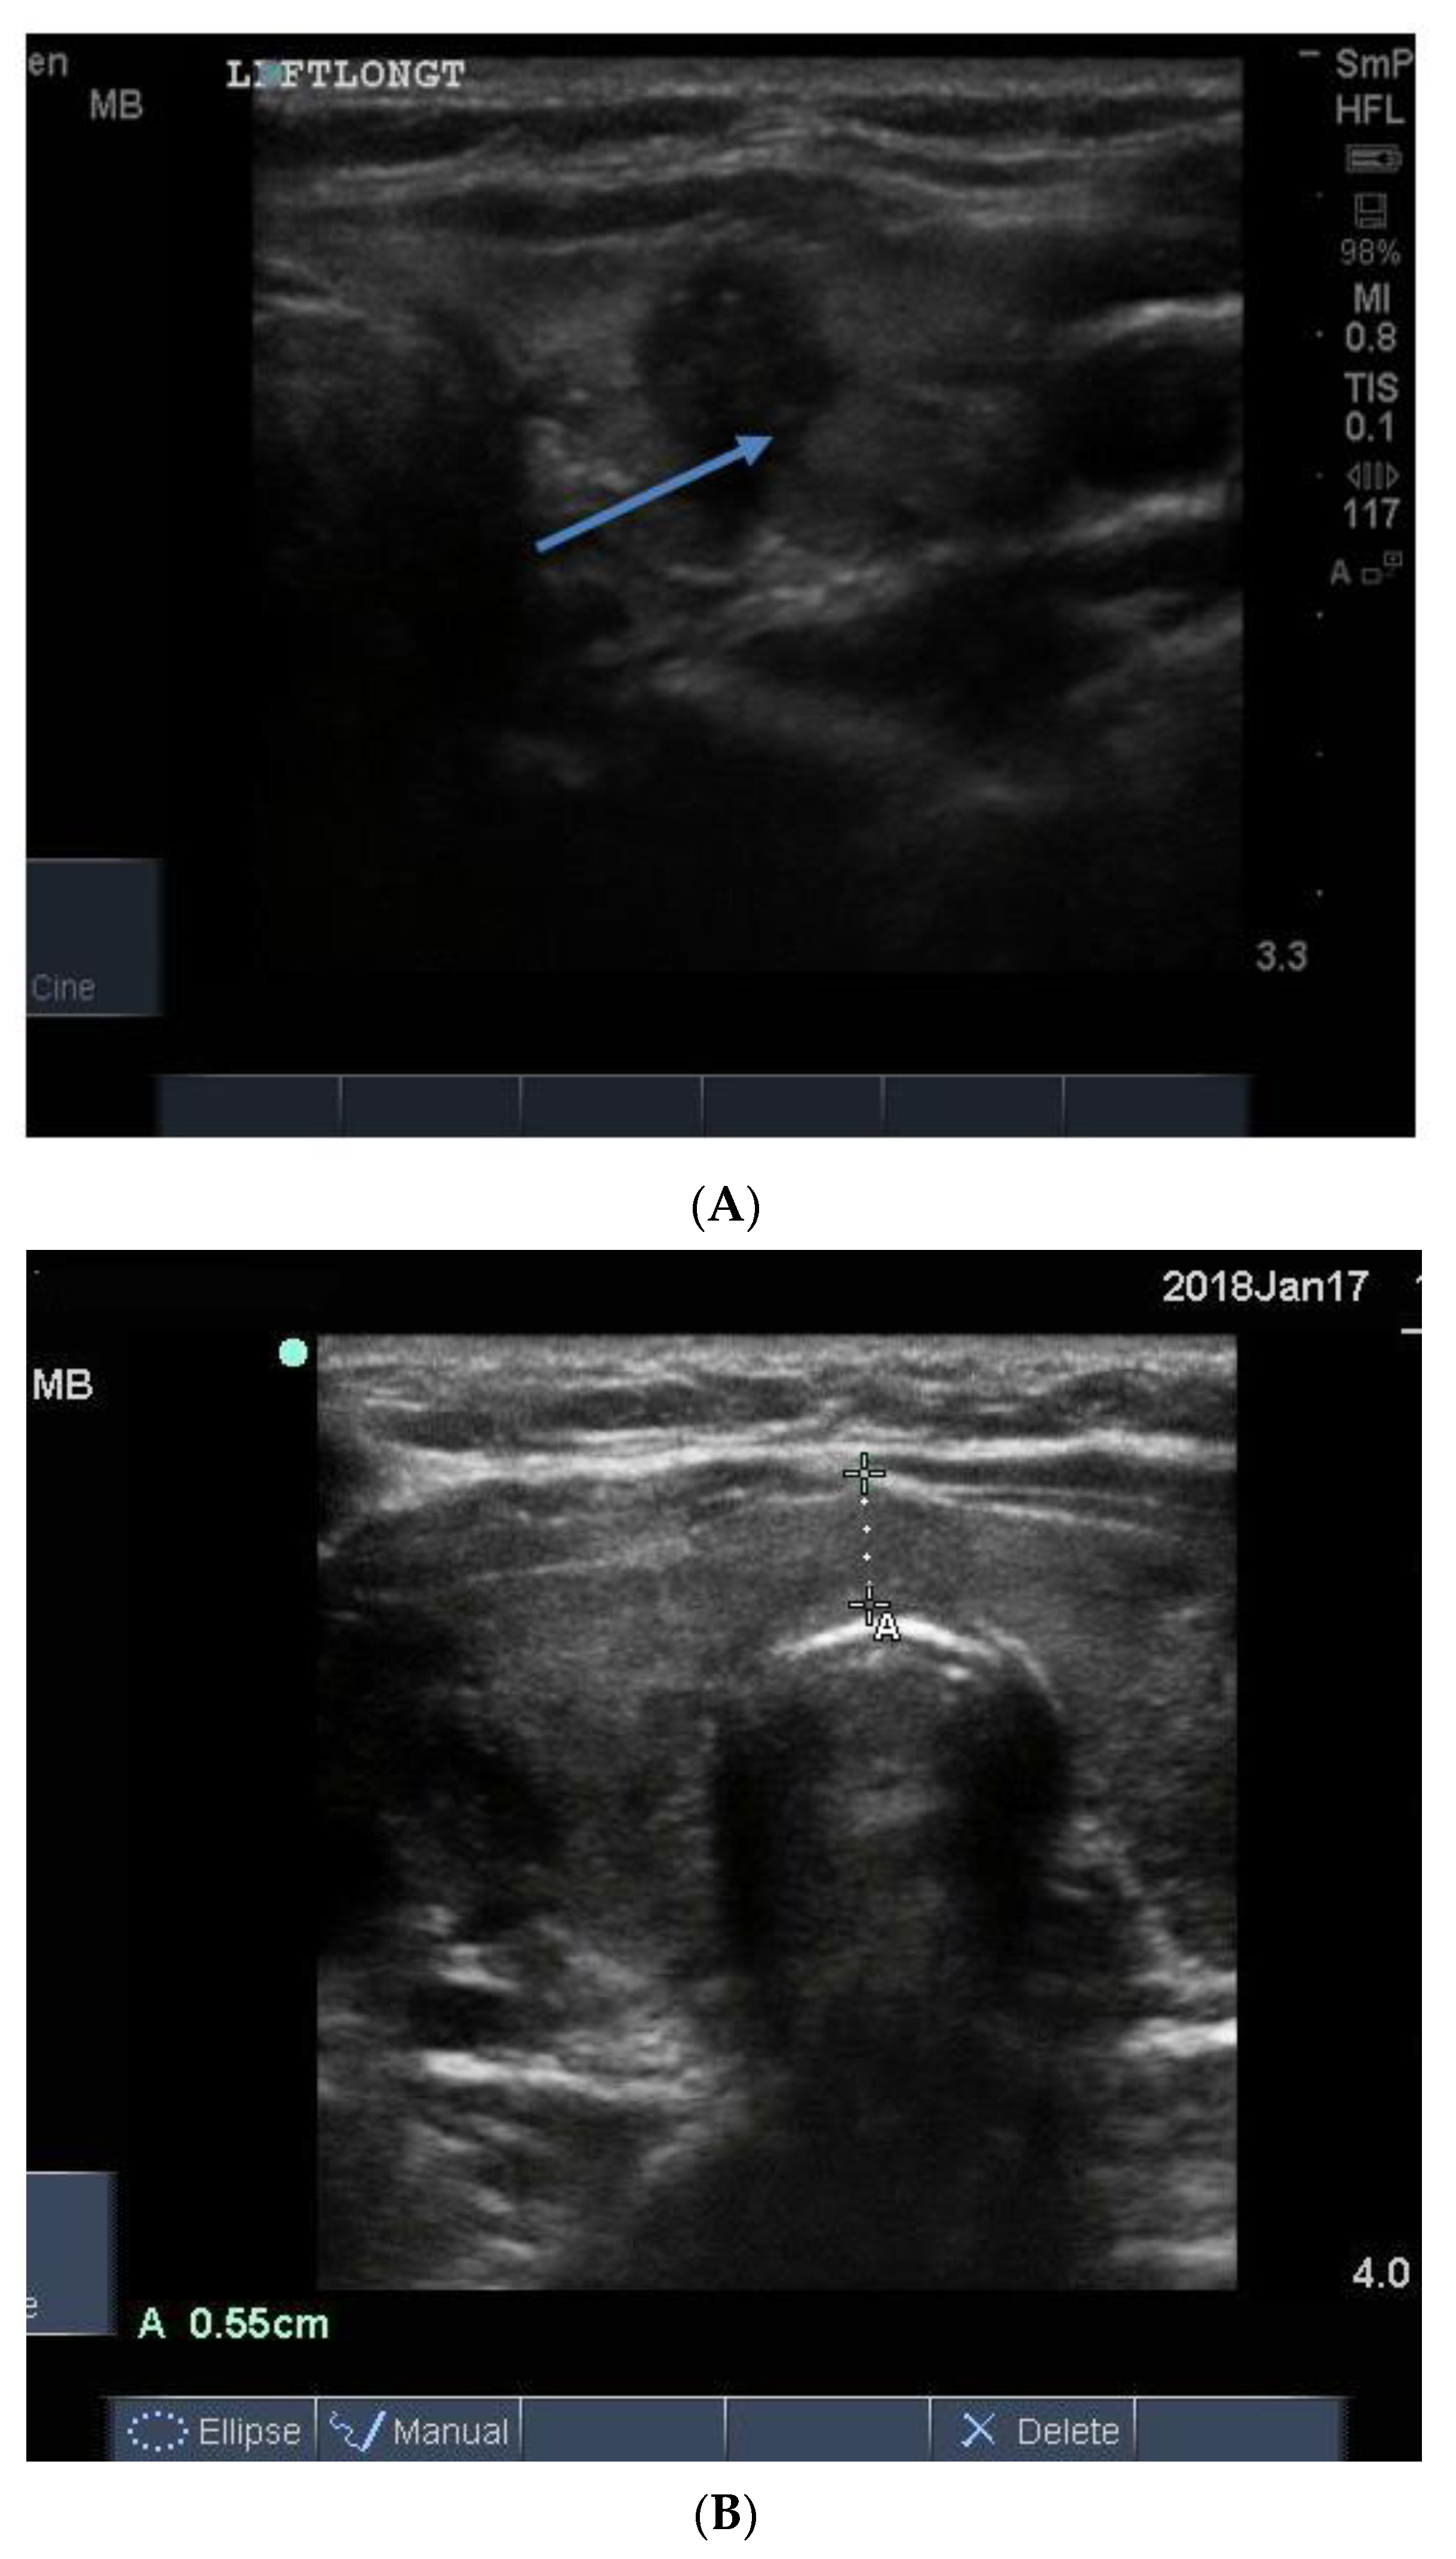

The blood supply in typical Graves’ disease is diffusely increased (and associated with a murmur), sometime up to 100 times normal, and the gland texture on ultrasound is usually heterogeneous (patchy) with a fine cystic appearance throughout, which reflects the diffuse nature of the inflammatory process (Figure 15). Following radio iodine treatment, the normal gland architecture is disrupted because the follicles are destroyed, and scar tissue predominates.

Figure 15. Thyroid ultrasound from two patients with Graves’ hyperthyroidism. In (A) is shown an example of early Graves’ hyperthyroidism manifest as multiple small inflammatory and lymphoid lesions, often described by the consultant radiologist as “nodules” blue arrow. In (B) is shown an enlarged thyroid, with a thick isthmus and a generalized patchy hypo echoicity due to the lymphocytic inflammation and thyroid cell proliferation. In (C) is shown the increased vascularity in the thyroid of the patient shown in (B).